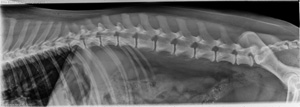

6 year old Australian Shepherd

Today's case is a 6-year-old male neutered Australian Shepherd dog. Tense abdomen, stiff gait. Proprioceptive deficits in the hind limbs. Pain on palpation of the thoracolumbar junction. Leave your findings in the comments. … [Read more...]